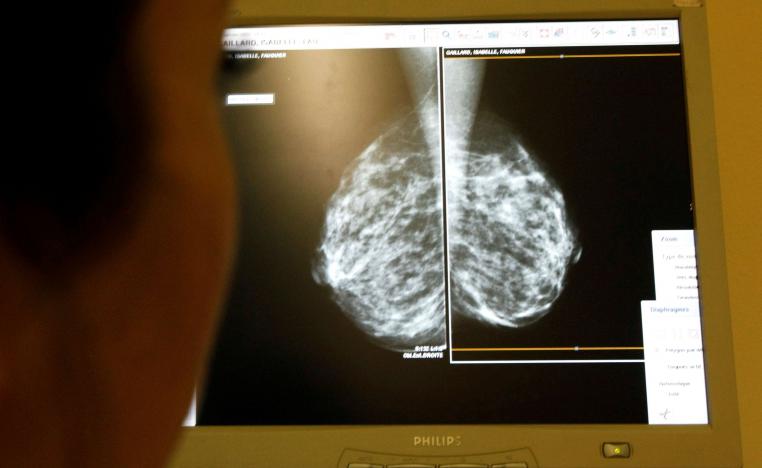

سرطان الثدي يتصدر الأورام الخبيثة الأكثر انتشارا عالميا